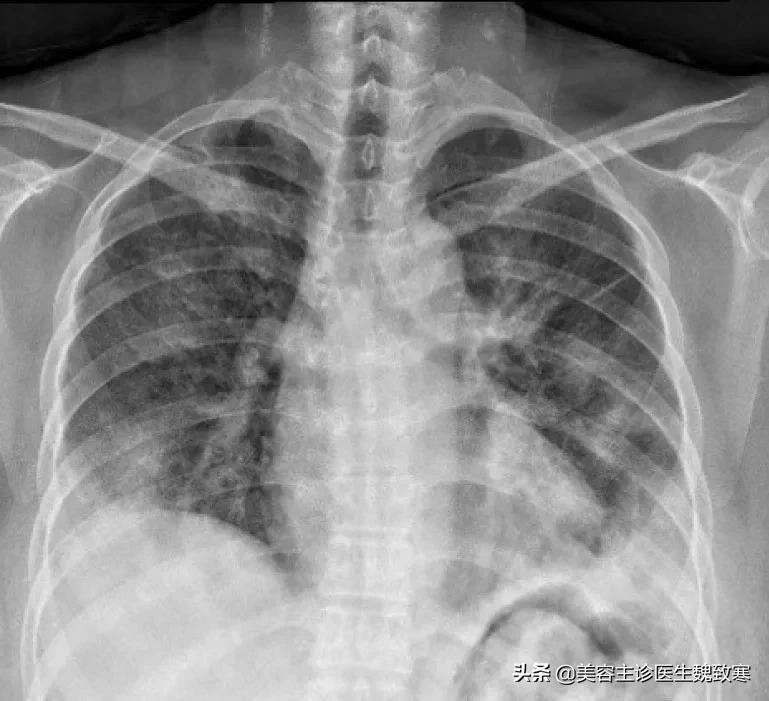

胸部X线表现为双侧弥漫性磨玻璃混浊(GGO)及实变。